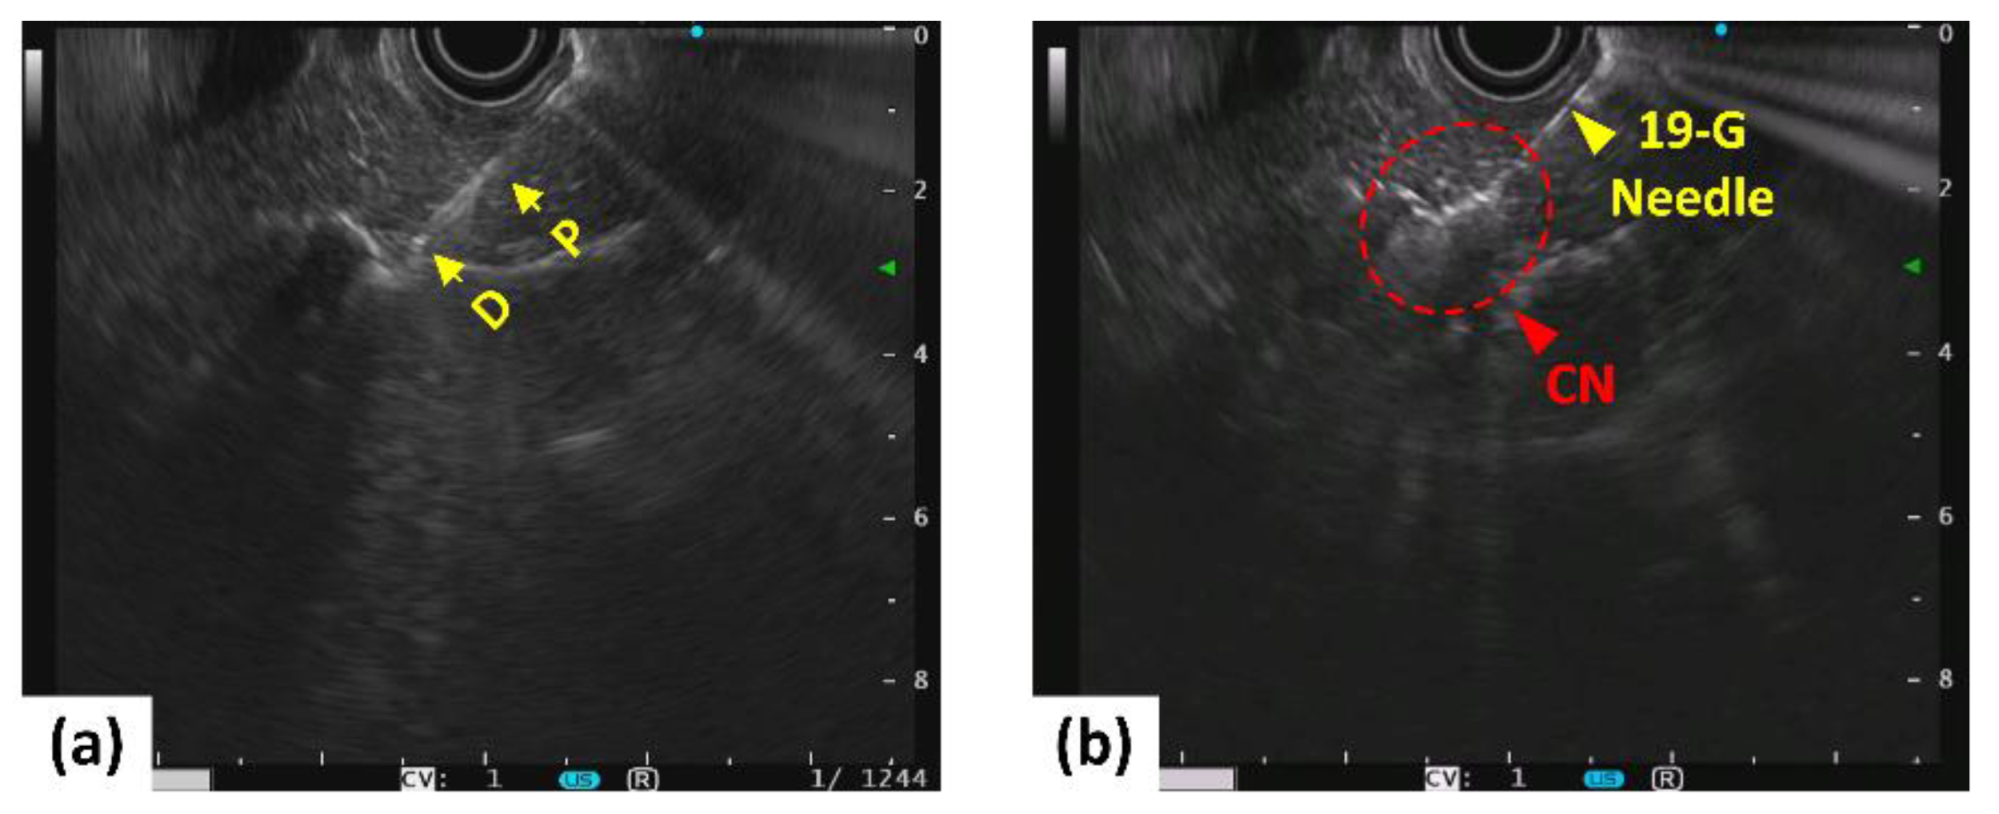

Figure 2 shows the EUS images captured after insertion of both the biopsy needle and diffusing applicator into porcine pancreatic tissue. Prior to laser irradiation, the position of the diffusing applicator in the pancreatic tissue was confirmed by EUS visualization (Figure 2a). Figure 2b presents whitish regions around the diffusing applicator in the treated tissue, representing coagulated necrosis (CN) after 5 W irradiation for 160 s. Video S2 shows the EUS monitoring of the CILA in the pancreas in a porcine model.

Figure 2.

EUS-guided LA on pancreatic tissue in porcine models before (left; (a)) and after (right; (b)) irradiation at 5 W for 160 s (P = proximal and D = distal ends of diffusing applicator; CN: coagulative necrosis).